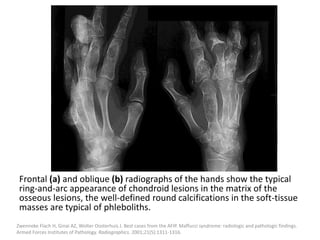

The best clue to identify a VM is the presence of phleboliths, these are

seen as small calcifications on radiography (a) and CT (b, c) and as

low signal small foci on all MRI sequences (d), the images presented

here correspond to three different patients.